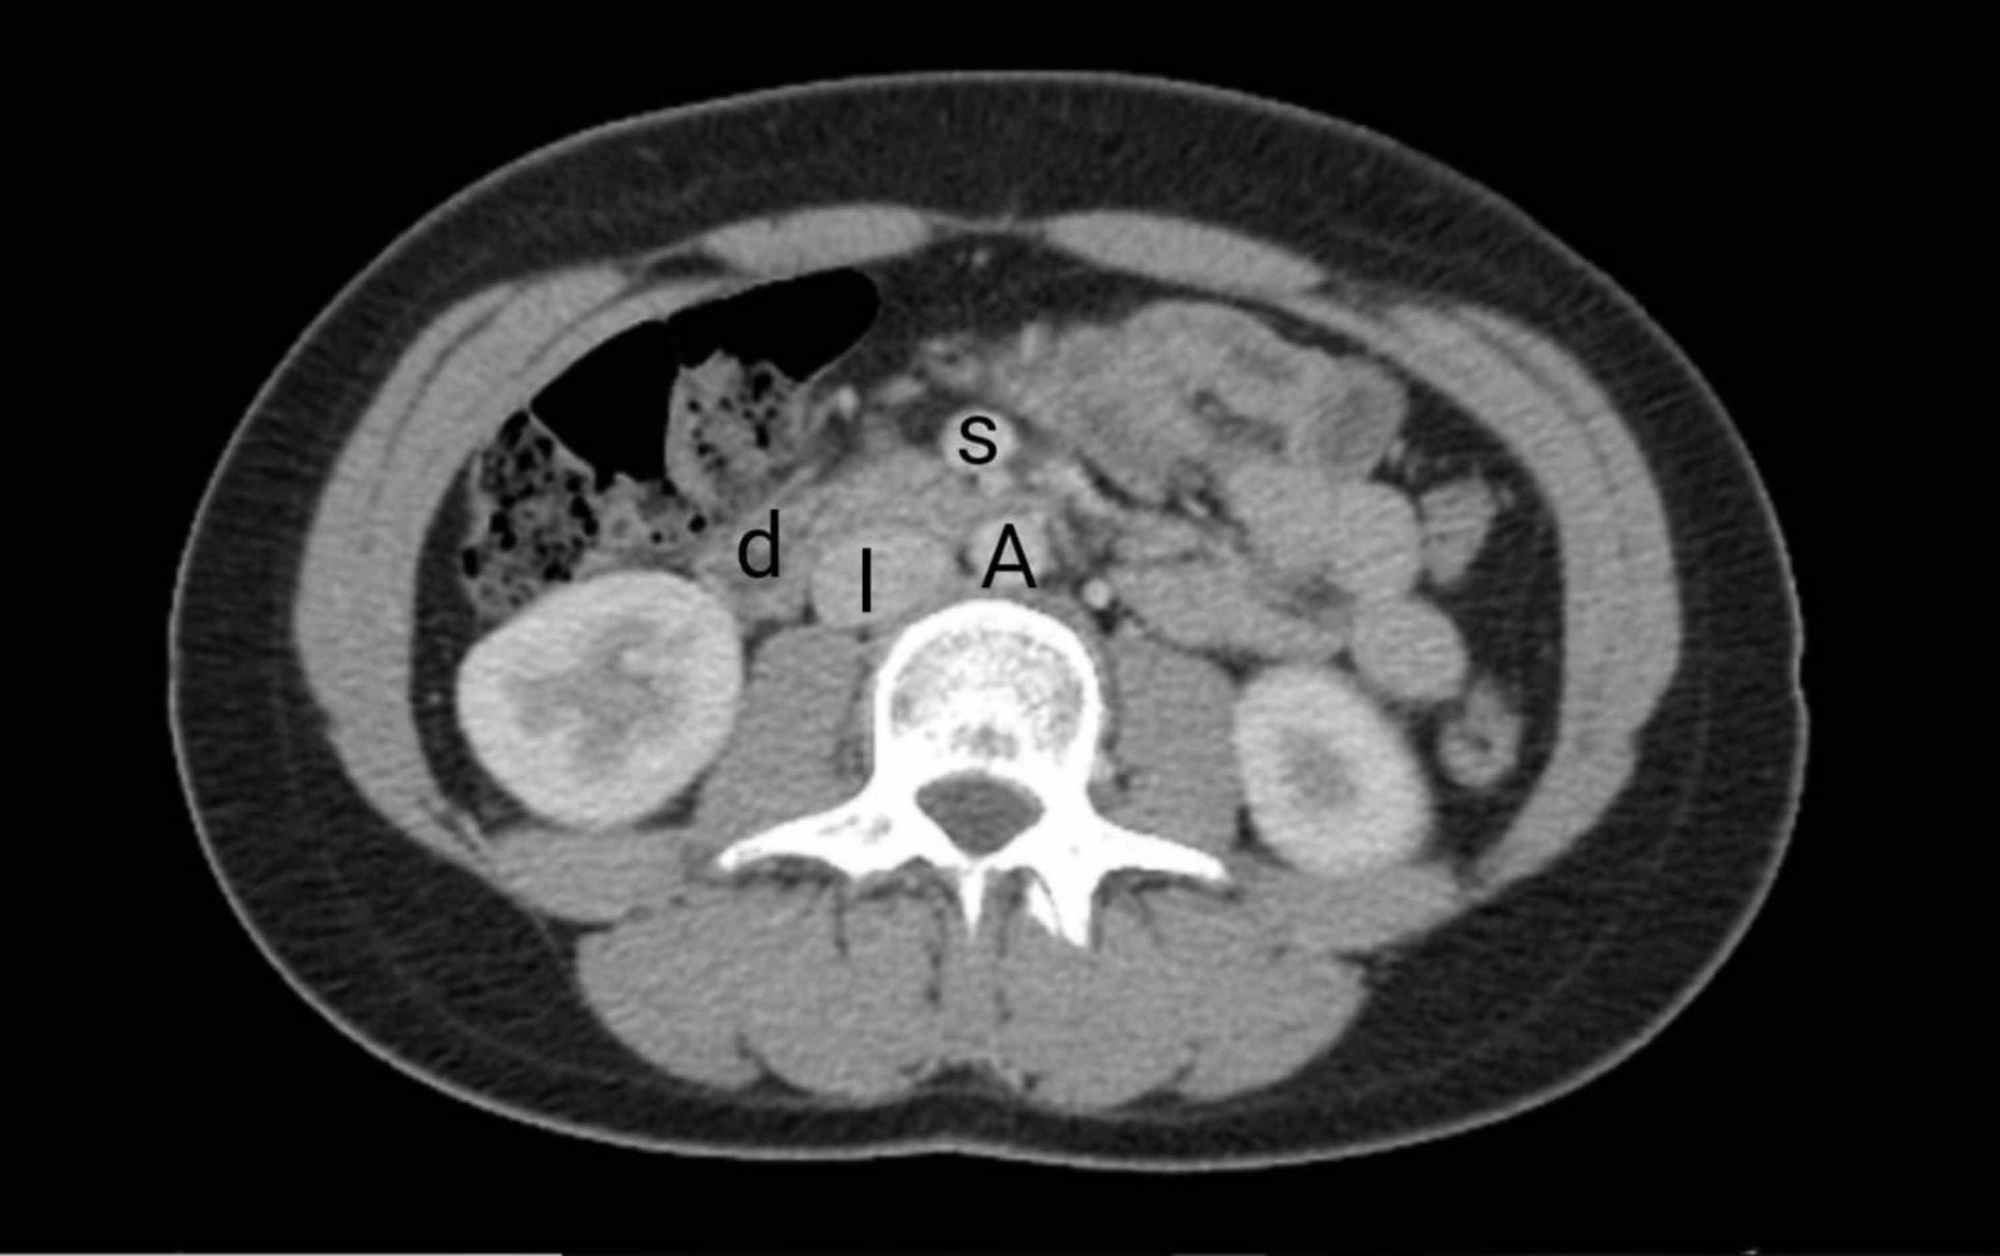

During this medical condition, the compression of the third and final portion of the duodenum occurs between the overlying superior mesenteric artery and the abdominal aorta. Wilkie’s syndrome is a potentially life-threatening and rare syndrome. This condition is also known; by various names such as cast syndrome, intermittent arterio-mesenteric occlusion, chronic duodenal ileus, or mesenteric root syndrome. SMA is distinguishable from a nutcracker syndrome which is the inveiglement of the left renal vein between the SMA and the abdominal aorta. However, the diagnosis is possible with both of these conditions. This syndrome is a rare cause of upper gastrointestinal obstruction.